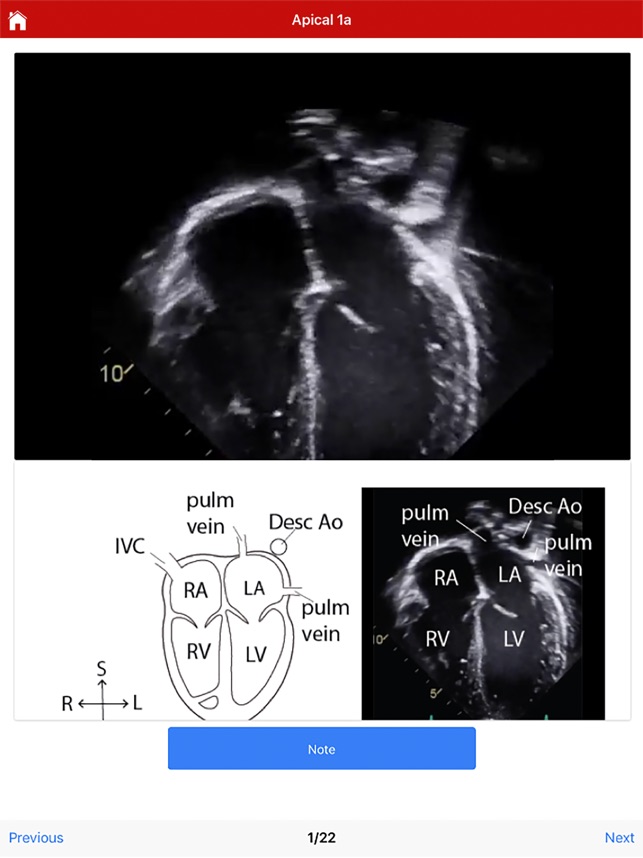

This educational tool, developed in connection with the University of Wisconsin-Madison, provides procedural guidance for performing a normal pediatric echocardiogram. The system delivers instructional content organized by four standard imaging views: subcostal, parasternal, apical, and suprasternal. To facilitate skill acquisition, the platform integrates multimedia assets, including video clips, static images, and technical illustrations. A user can navigate through a protocol sequentially or access specific views directly. Procedural instructions are displayed automatically upon view selection and can be supplemented with additional notes accessible through the interface.